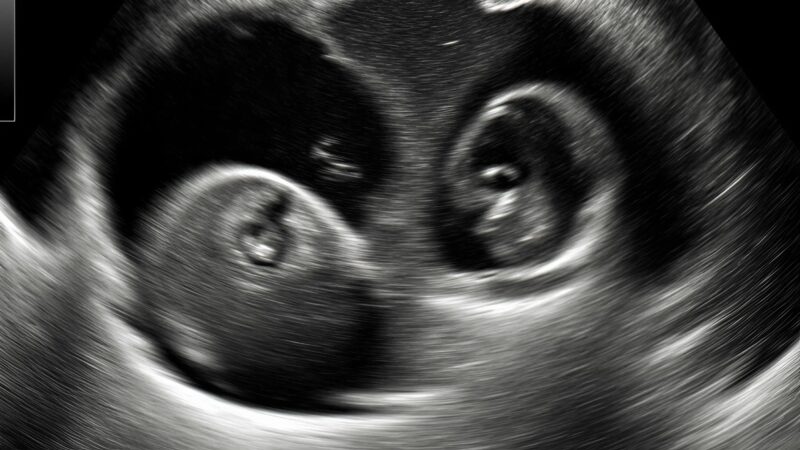

“Uh… hmm…” he muttered, scanning the screen with a careful precision that made me lean forward, my heart skipping beats . “You’re… well… you’re having twins.”

I froze, blinking, as if the words had physically struck me . “Twins?” I whispered, my voice barely audible. My mind was a whirlwind of emotions: shock

Tears sprang to my eyes , but not just from fear or shock — these were tears of happiness, a release of all the tension I hadn’t realized I was carrying. Two tiny lives, growing inside me at the same time

. I could already imagine the tiny kicks, the laughter, the double the trouble, and double the love